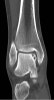

CT : 거골의 박리성 골연골염(Osteochondral lesion of talus)